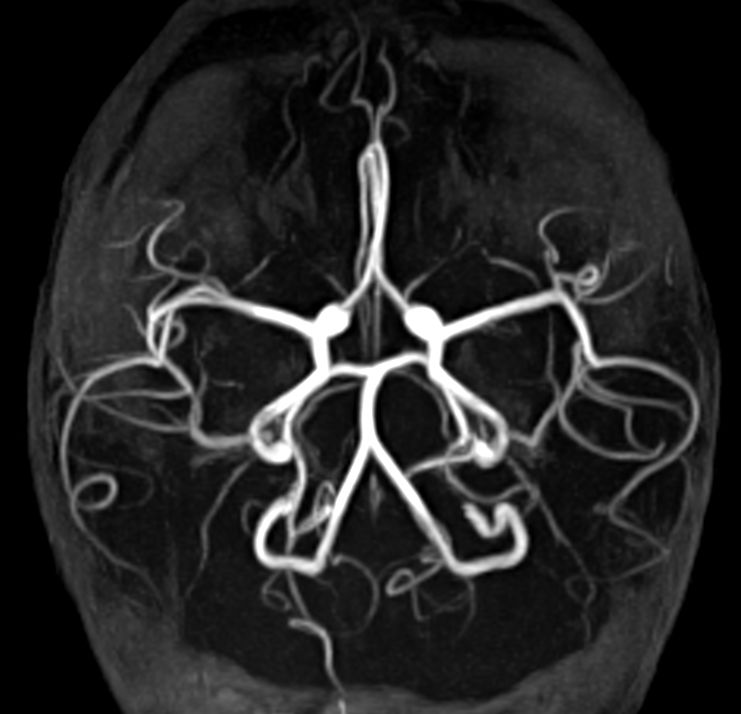

Coronal 3D TOF (MIP)